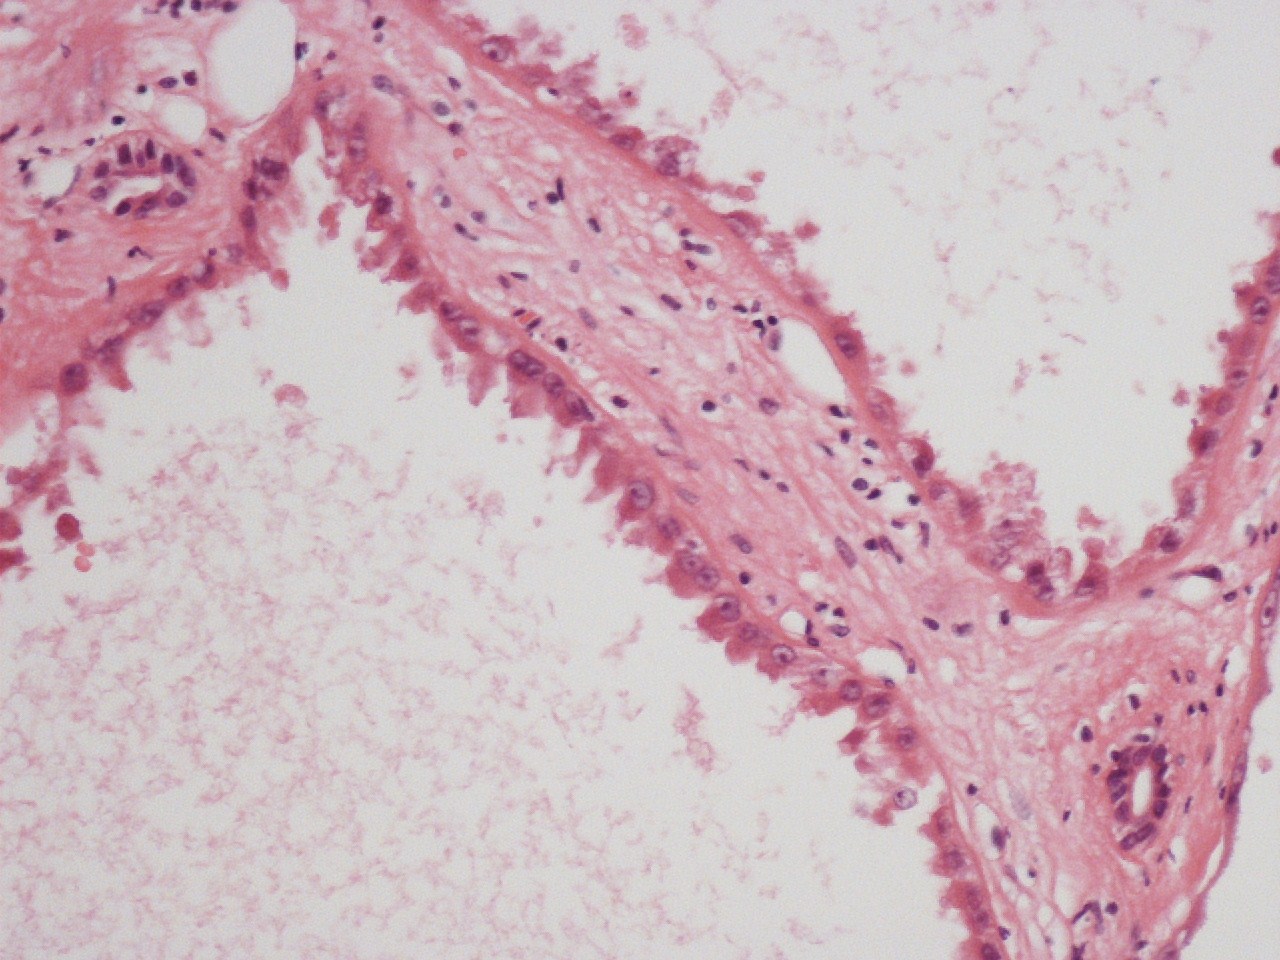

Case description (by case creator):

Renal tumor from a 48 year old male. The tumor was 7.3cms in diameter and had a grey spongy morphology. It is composed of cysts of varying sizes. These are lined by a single layer of tumor cells. these are variously cuboidal, columnar or on occasion hob-nailed. The cytoplasm is eosinophilic and faintly granular. Nuclei are centrally placed and although showing minimal pleomorphism do have prominent single nucleoli. Mitoses are rare.